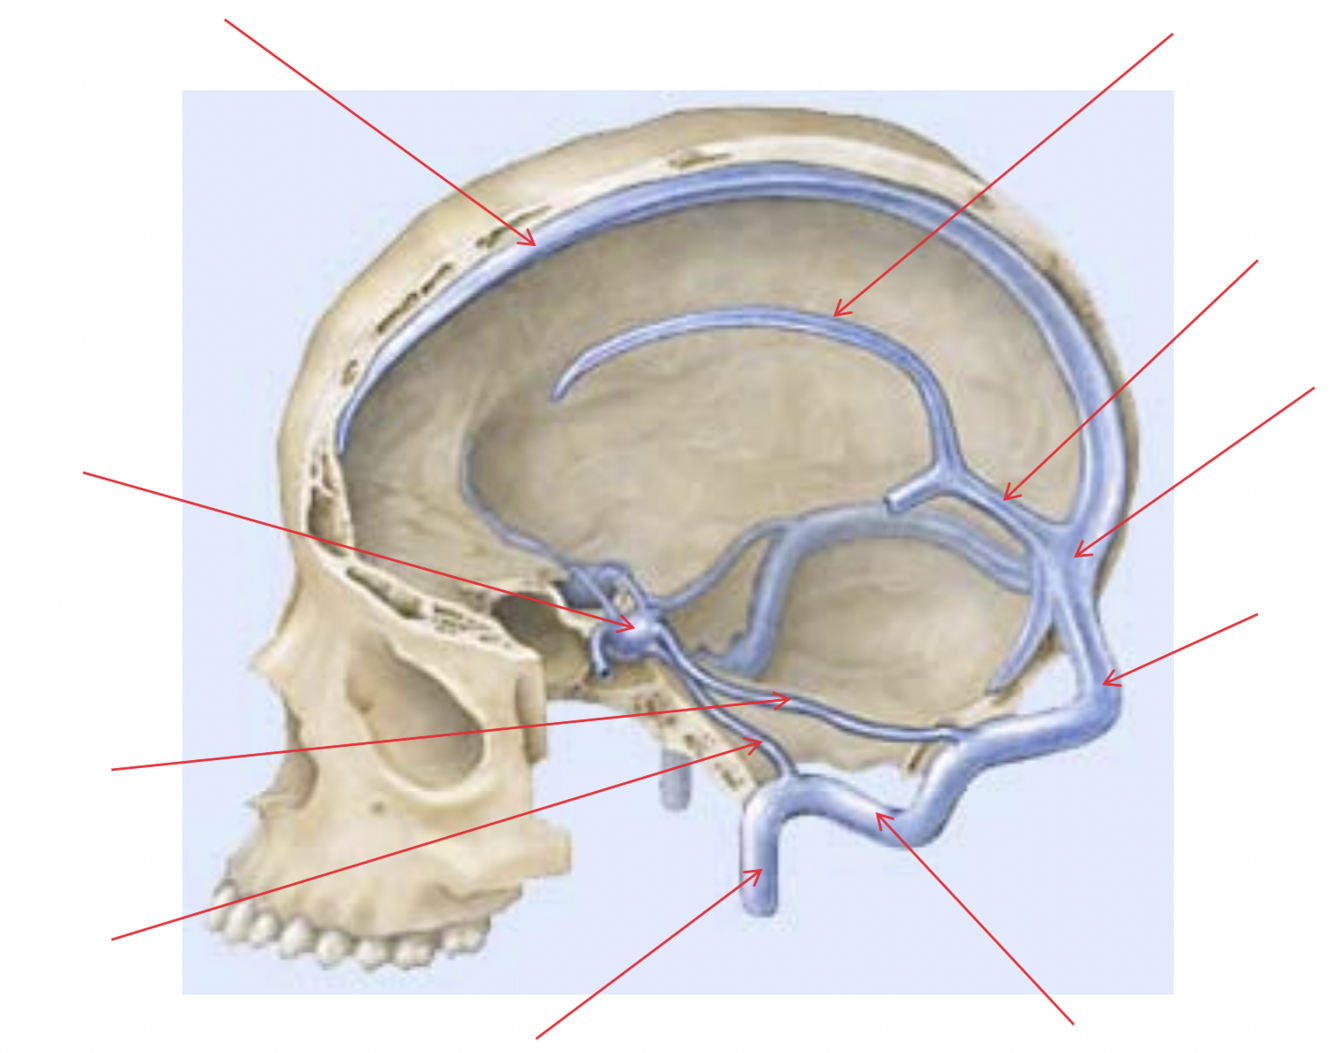

Where is the superior sagittal sinus?

Joins transverse sinus

Arachnoid villi drain CSF into superior sagittal sinus

Where is the inferior sagittal sinus?

Joins straight sinus

16

Where is the straight sinus?

Within tentorium cerebelli

Joins left transverse sinus

17

Where is the transverse sinus?

Continuous with straight sinus

18

Where do sinuses join?

Confluens

Q

A

Forward continuation of transverse sinus

Opens into internal jugular vein

20

Where is the cavernous sinus?

Lateral to pituitary gland

Drains into sup. and inf. petrosal sinuses

21

Where does the cavernous sinus drain into?

Transverse sinus (superior petrosal) and internal jugular vein (inferior petrosal)

22

Name the sinuses

There are 6

Sup. sagittal

Inf. sagittal

Straight

Transverse

Sigmoid

Cavernous